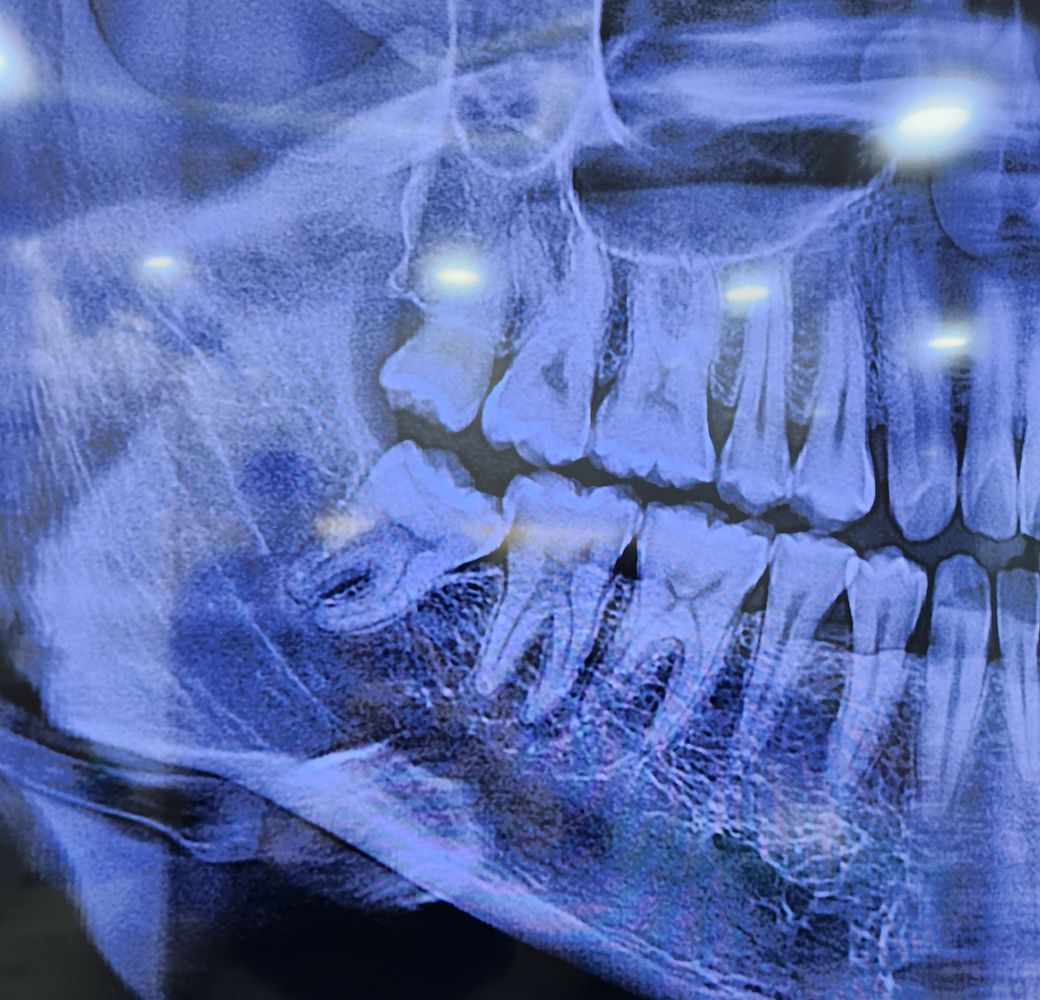

엑스레이 찍었는데 신경치료 해야하나요?

사랑니쪽이 썩은것같아서 치과에 갔는데 엑스레이 보시더니 사랑니앞쪽 어금니 옆면에 음식물이 많이 껴서 신경치료 필요할것같다고 하시더라고요

신경치료가 정말 필요한건가요?

신경치료 말고 치아를 보존할수있는 치료가 있는지 궁금합니다

• 1번 째 사진

사랑니 때문에 어금니 뒷쪽에 충치가 생겼습니다. 뒷쪽면 충치는 신경치료까지 해야 하는 경우가 종종 생깁니다. 일단 신경치료 안할 수도 있으니 치료는 시작해야 합니다.

충치가 진행이 된 것으로 보이며 신경치료를 해야할지 인레이도 마무리될지는 치근단사진이 필요합니다.

신경치료 가능성이 높아 보이긴 합니다. 일단 사랑니 발치를 하시고 나서 다시 작은 사진을 찍어 보셔야될것같습니다.

사랑니가 옆 어금니를 눌러 충치를 유발한 것 같습니다. 충치가 얕지는 않습니다. 신경치료 가능성이 있되 일단은 사랑니빼고 충치치료해볼 수 있을 것 같습니다.